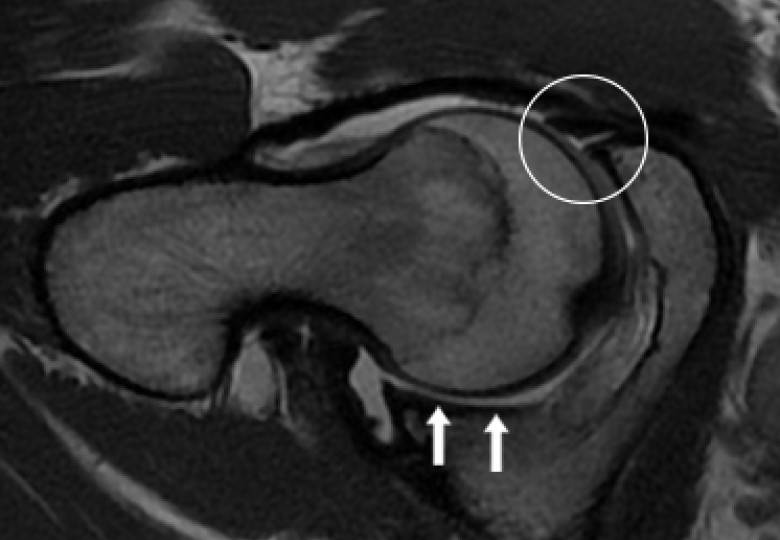

• Labral hyperplasia ( enlargement of the cartilage at the margin of the hip socket) was a predictor of microinstability.

• Increased acetabular anteversion (a measure of the angle of the hip socket) and decreased lateral centre edge angle (LCEA, a measure of hip socket coverage) were associated with microinstability.